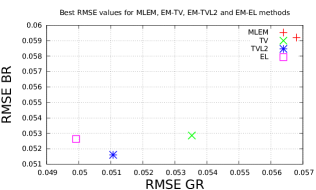

To quantify obtained reconstructions we used averaged over all noise realizations RMSE (23) values in the bone region (BR) and in Gaussian regions (GR). All regularization parameters were carefully selected by comparing the mean of all RMSE values over all noise realizations in GR and BR (see Fig. 8).

After estimation of regularization parameters we performed twenty reconstructions for each method with various Poisson noise distributions. The mean values for GR and BR over all noise realizations are shown in Fig. 9. This result proves that the EL penalty is very successful in resolving smooth features (six Gaussians in this case) and also quite competitive for the BR (lower RMSE value than for TV).